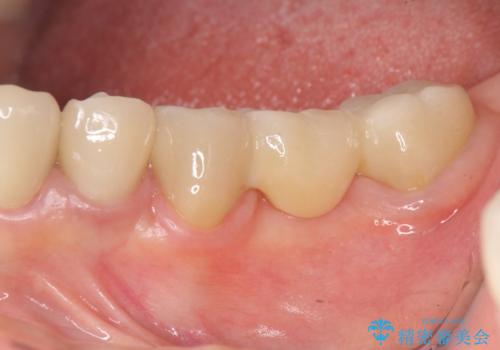

精度の高いジルコニアブリッジの製作に加え歯茎にぴったりとそわせたオベイトポンティック形態とすることで清掃性・審美性に優れたブリッジを製作します。

歯ぐきの形態にそわせ、凸型でくぼみのないオベイト型のポンティックはプラークの溜まりにくく審美性も達成できるポンティック形態です。